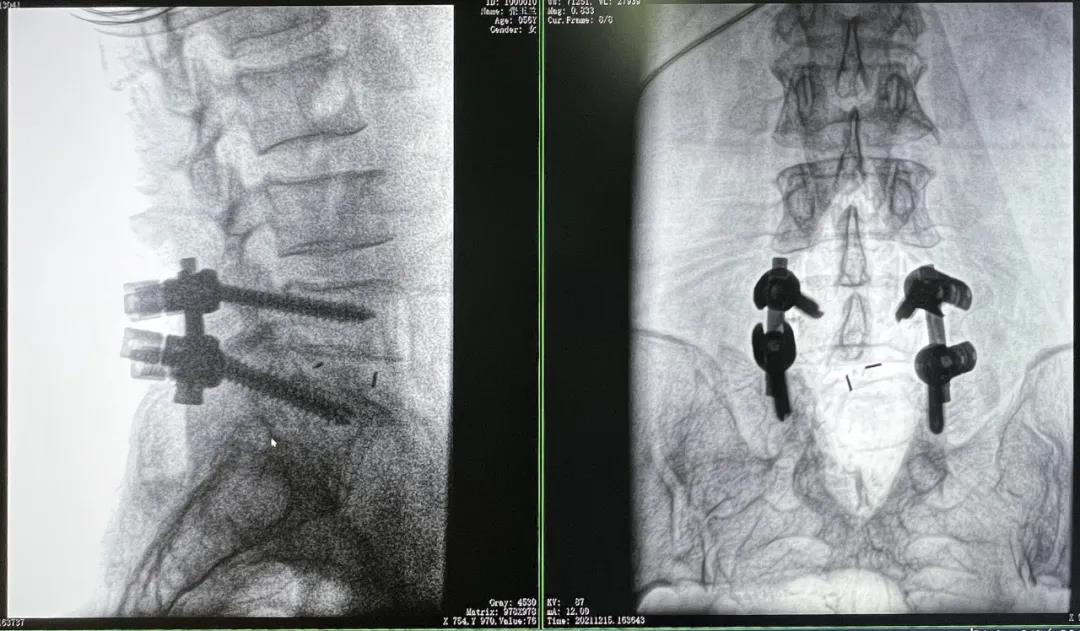

患者1:女性,56歲,L5/S1椎間盤椎板減壓+釘棒固定術(shù)

患者下腰部疼痛,活動受限,伴有左下肢疼痛5年,久站或彎腰干活時疼痛加劇,臥床休息后疼痛癥狀緩解,近一個月情況加重,需行椎板減壓+釘棒固定術(shù)。

3D C形臂擺位及手術(shù)前二維影像

醫(yī)生在影像引導(dǎo)下在L5/S1椎弓根處打入醫(yī)用螺釘

術(shù)中快速生成橫斷面、矢狀面、冠狀面斷層圖像和三維立體圖像